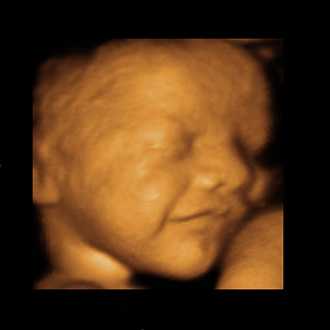

3D/4D SONOGRAPHY

3D/4D SONOGRAPHY (Live)

Built on a digital platform, the Voluson 730 utilizes advanced signal processing technology to ensure optimal image quality for high-resolution 2D, volumetric 3D and real-time 4D imaging. Image quality is further enhanced with Harmonic imaging, spectral, color and Doppler imaging,as well as our latest advance – Compound Resolution Imaging.

• High-resolution 2D, volumetric 3D and real-time 4D imaging